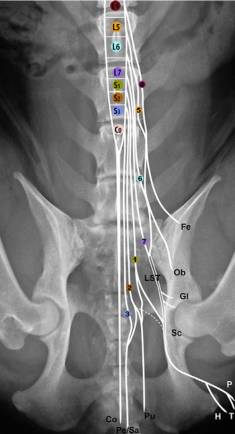

Anatomie

Der Conus medullaris liegt im kaudalen Anteil vom L6 bis zum kranialen Anteil vom L7. Bei kleineren Hunden weiter kaudal. Der Durasack geht bei 80% der Hd bis ins Sakrum. Die Cauda equina entspringt am Conus medullaris und reicht vom L6 bis zum Cd5.